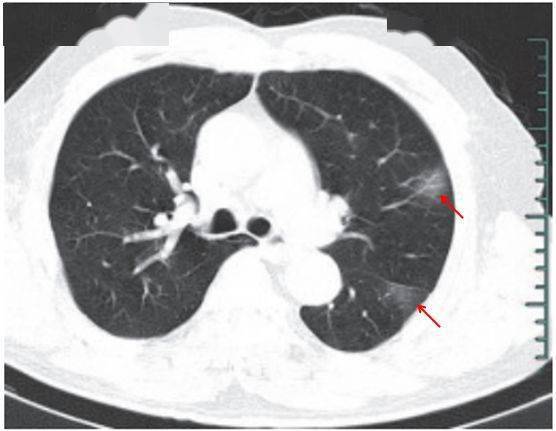

(一)病灶分布

病灶以 肺外围背侧为主,以两肺下叶为著,与胸膜常紧贴,提示新冠肺炎病变多首先侵犯皮层肺组织的细支气管及肺泡上皮, 病灶分布逐步从外周向中央扩展(图 2-1)

图2-1 早期病灶多数分布贴近胸膜( 共4张 )